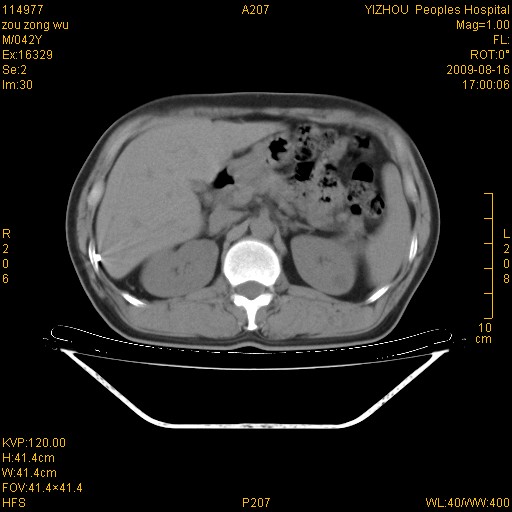

以下是引用zjzjr在2009-8-17 10:42:00的发言:[br]右侧间质性肺炎伴纤维化,右肺下叶肺囊肿伴感染(不除外外伤后引起),右肺野及胸壁软组织\\肝内见多发斑点状,中枪了吧.右侧胸膜肥厚\\粘连.